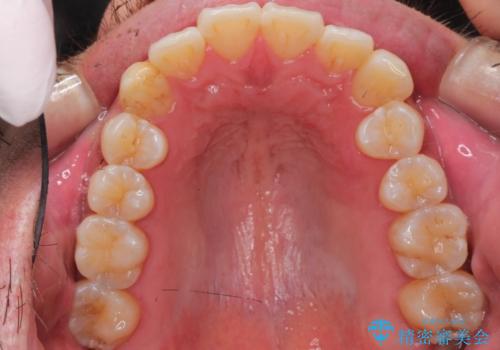

【インビザライン】前歯の凸凹を解消。

- 前歯の凸凹を主訴に来院されました。

もともと、顎が左にシフトしていたので正中が合わないことを説明した後、矯正を開始しています。

短期間で前歯のがたがたがきれいになり、満足していただけました。